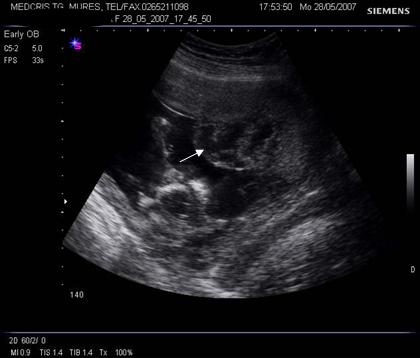

Fig. nr.212. Spatiu chistic subchorionic , la o sarcina de 12 saptamani. ( sageata ), placenta inserata pe peretele anterior uterin

Fig nr.213 Vascularizatie a peretelui uterin subplacentara, ce nu trebuie confundata cu hematomul retroplacentar

Fig. nr.214 Placenta normala la 27 saptamani, cu zona lacunara circumscrisa, intr- o protuberanta ce imita o formatiune tumorala placentara

Fig. nr. 228. Circulara de cordon in jurul gitului , la o sarcina de 30 sapt., demonstrata la Doppler color